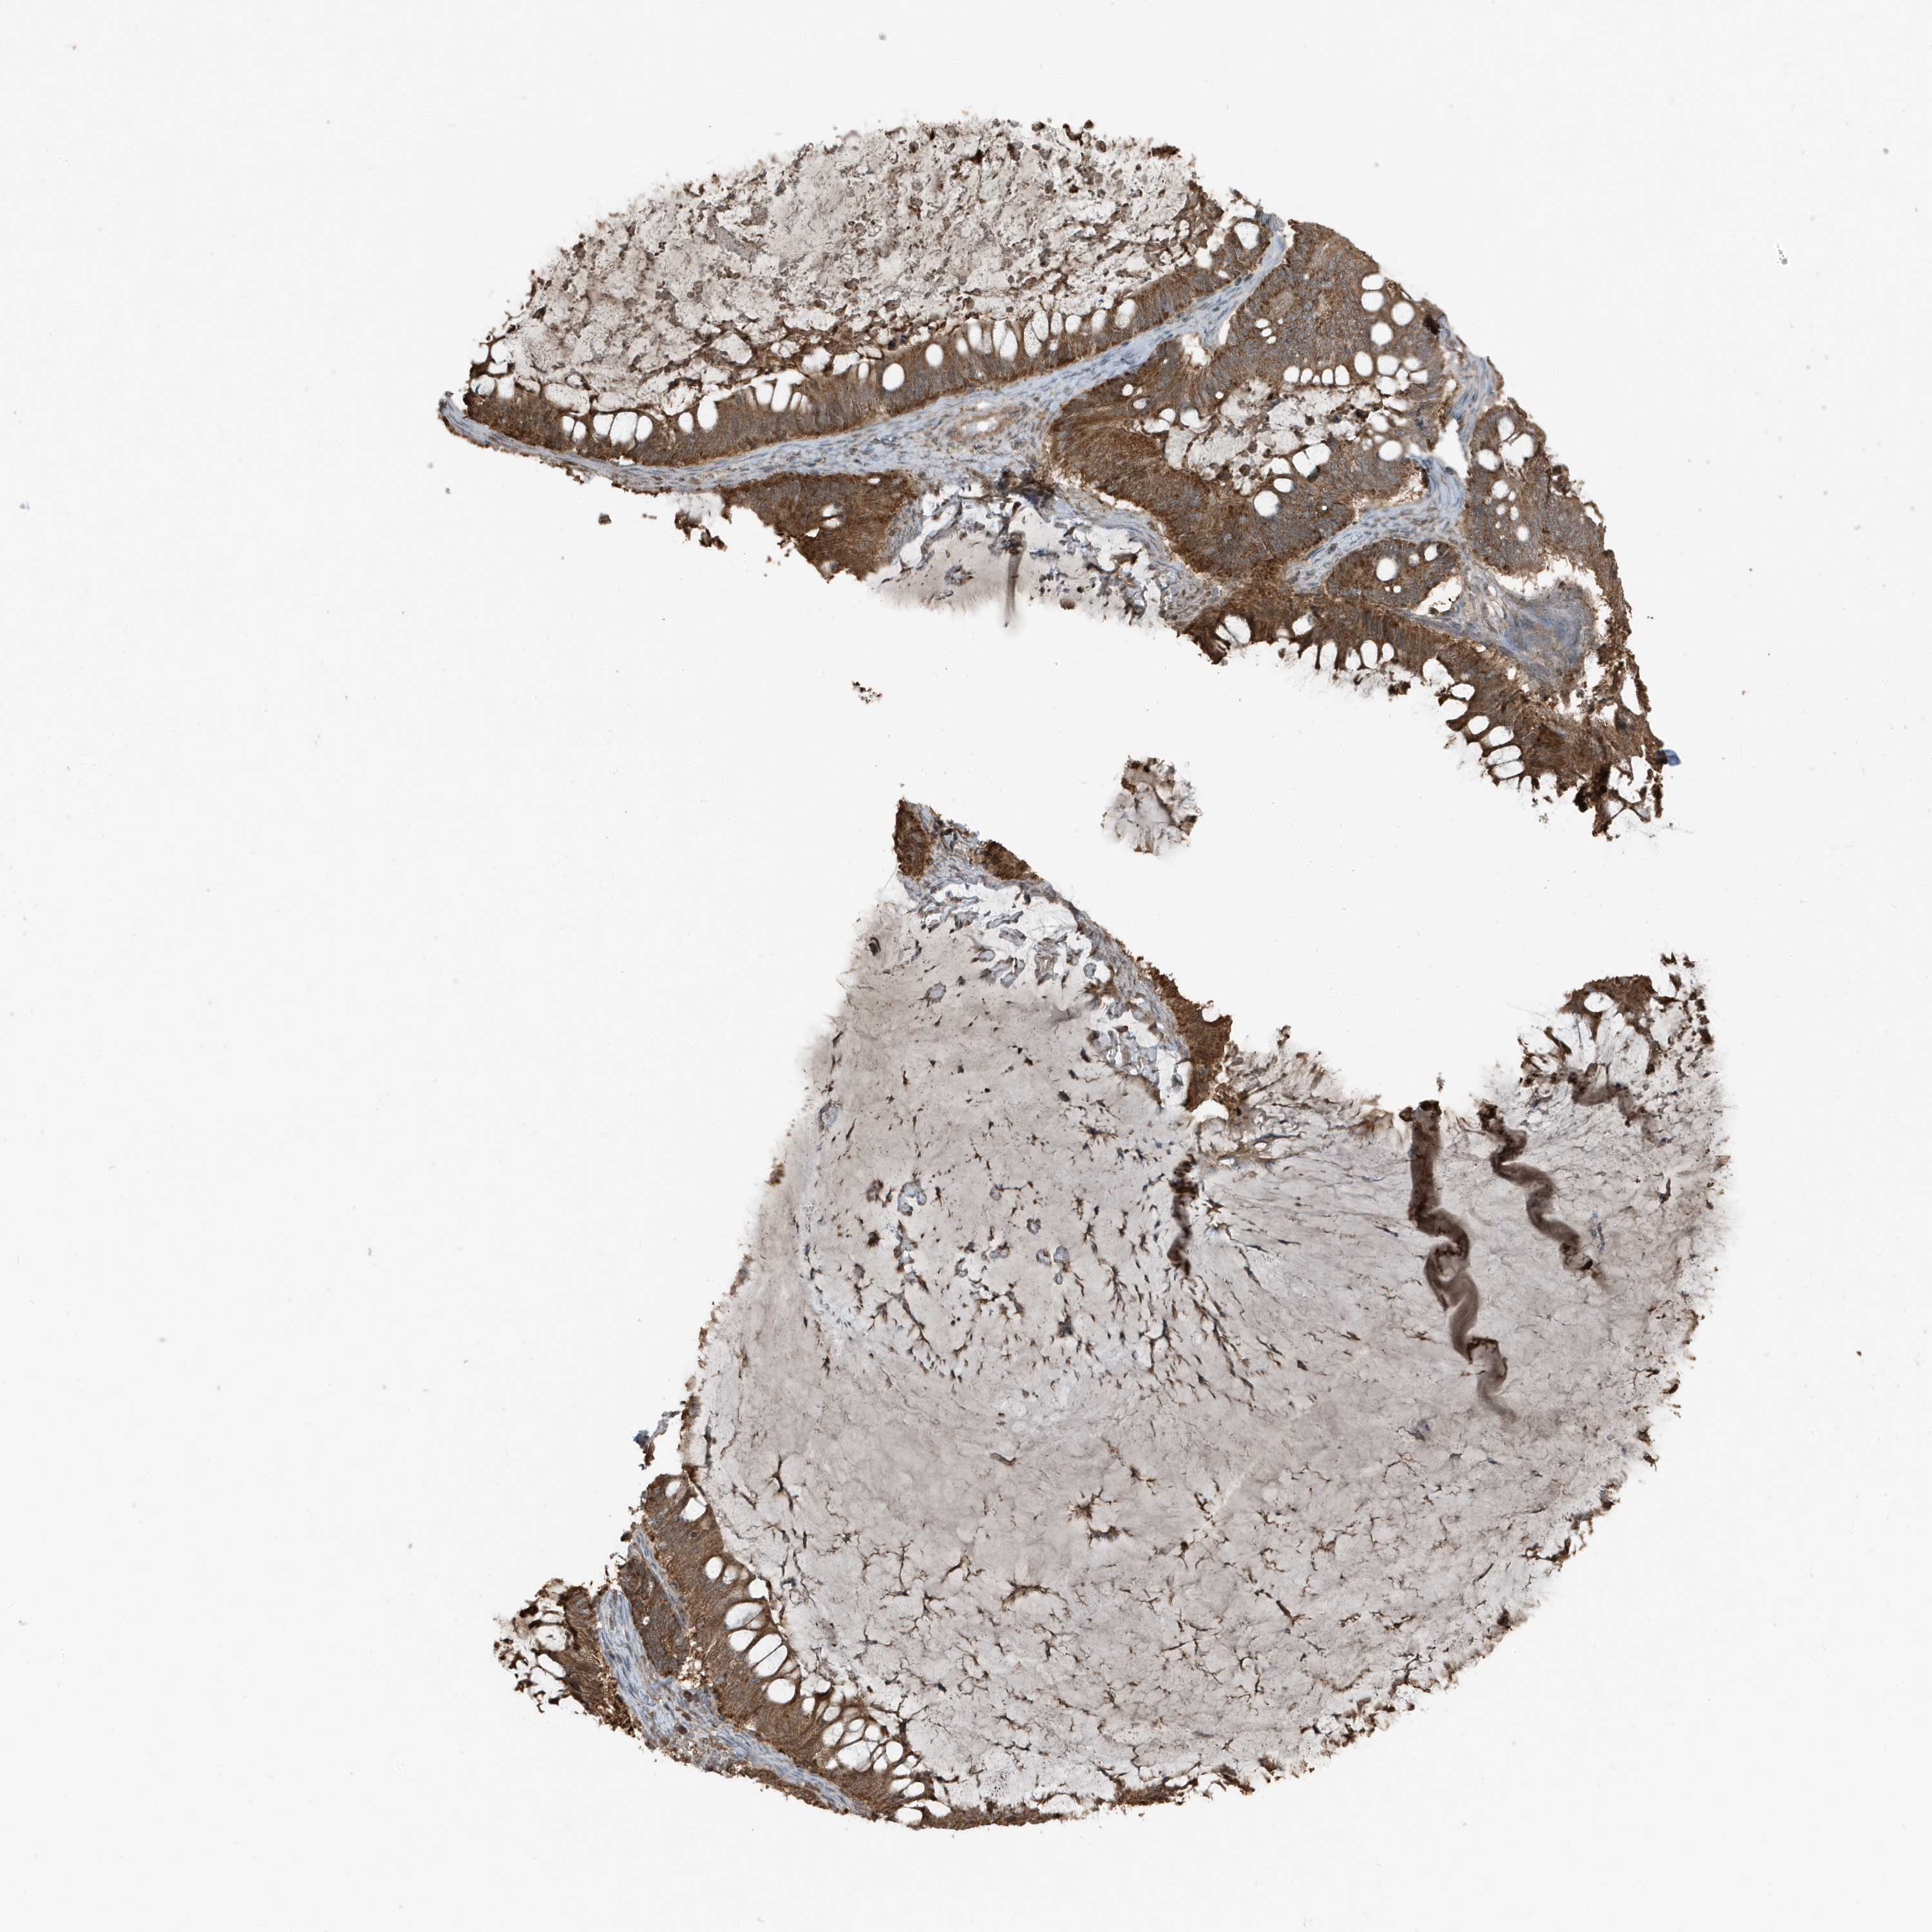

OVARIAN CANCER - Protein expressioni

A mouse-over function shows sample information and annotation data. Click on an image to view it in a full screen mode. Samples can be filtered based on level of antibody staining by selecting one or several of the following categories: high, medium, low and not detected. The assay and annotation is described here.

Note that samples used for immunohistochemistry by the Human Protein Atlas do not correspond to samples in the TCGA dataset.

Antibody stainingi

Antibody staining in the annotated cell types in the current human tissue is reported as not detected, low, medium, or high, based on conventional immunohistochemistry profiling in selected tissues. This score is based on the combination of the staining intensity and fraction of stained cells.

Each image is clickable and will lead to virtual microscopy that enables deeper exploration of all samples and also displays staining intensity scores, fraction scores and subcellular localization as well as patient and tissue information for each sample.

Antibody HPA035258

Cystadenocarcinoma, serous, NOS

Carcinoma, endometroid

Cystadenocarcinoma, mucinous, NOS

Carcinoma, NOS